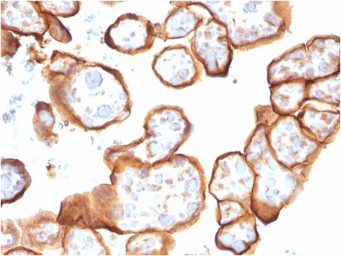

IHC-P analysis of human placenta tissue using GTX35108 Thrombomodulin antibody [THBD/1591].